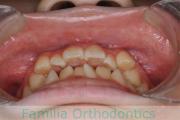

No.22V-409

- 叢生

- 16歳

- 女性

- 抜歯部位

- 上:

- 44

- 下:

- 8|58

- 主な使用装置:

- FEA

- 治療にかかった費用:

- 86万円

八重歯を治したいということで来院されました。下あごの左ずれのある上顎前突(出っ歯)・叢生(でこぼこ)でしたので、上は左右から、下はで左のみ小臼歯を抜歯して、歯科矯正用アンカースクリューとマルチブラケット法にて治療を行いました。2年強、30回程度の通院が必要でした。

上下とも前歯の叢生(でこぼこ、凹凸、ガタガタ)があるため、保定を怠ると後戻りのリスクがあります。